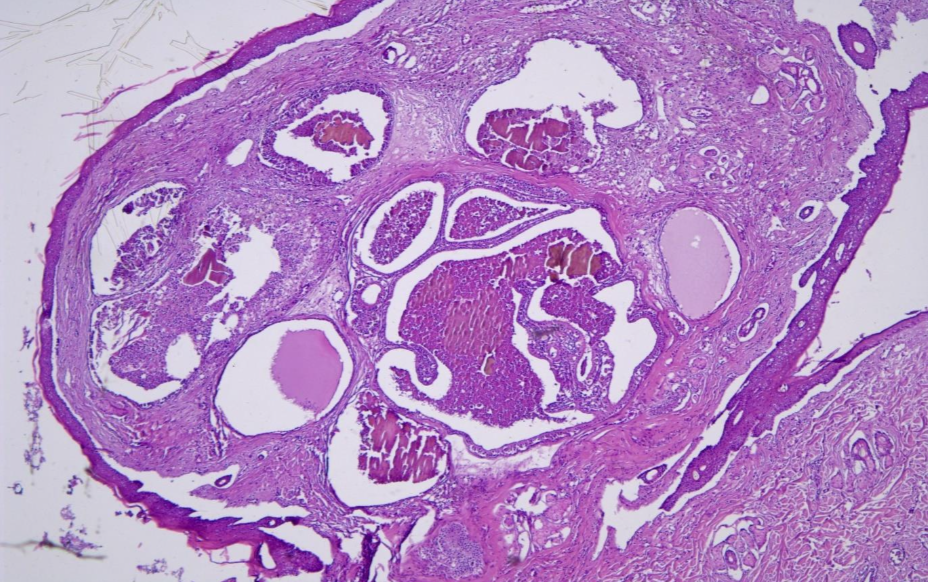

The deep dermis was expanded by an unencapsulated, well-circumscribed, multilobular neoplasm composed of two populations of cells (Fig. 1). The first population was composed of cuboidal to columnar cells forming varisized islands and well-differentiated tubules supported by a dense fibrovascular stroma. Neoplastic cells had indistinct cell borders, a small to moderate amount of granular eosinophilic cytoplasm (Fig. 2).

Within tubules, neoplastic cells frequently form few papillary projections into tubule lumina. Tubules contained necrotic debris and fragmented neutrophils. Ceruminous gland proliferation has areas of ectasia and hyperplasia as well as regional hyperplasia of sebaceous glands and pleocellular otitis externa.

Conclusion: Ceruminous gland adenoma